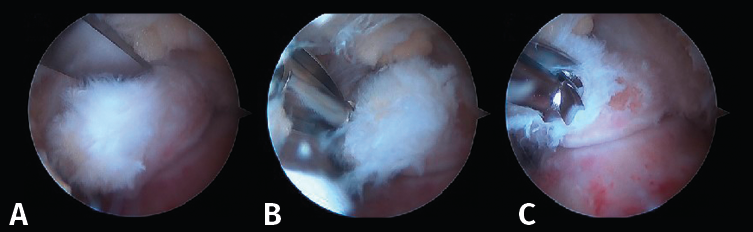

- Primer paso: retirar el LPAP, completamente en caso de PPAH y parcialmente en caso de OT. La resección del tejido ligamentoso se realiza apoyando la ventana del sinoviotomo contra el lateral del PPA (Figuras 4 A, B y C).

- Segundo paso: eliminar el tejido blando en la parte superior del PPA. La ventana del sinoviotomo se gira 90° para apoyarse sobre la parte superior del PPA. Con ello, se realiza la artrotomía tibioastragalina y se escinde la cápsula hipertrófica de la articulación posterior. Es importante realizar movimientos en plano horizontal para preservar la continuidad del ligamento intermaleolar y evitar una artrotomía de trazo vertical que podría seccionar inadvertidamente dicho ligamento (Figuras 5 A, B y C).

- Tercer paso. El sinoviotomo se gira ahora para que la ventana vuelva a mirar la cara medial del PPA. En este momento, el tendón FHL permanece medial al sinoviotomo y opuesto a su ventana. Podemos así seccionar el retináculo del FHL con el sinoviotomo o mediante una pinza de tipo basket (Figuras 6 A, B y C).

Figura 4. A: imagen artroscópica que muestra el ligamento peroneo-astragalino posterior (LPAP) (1); B: resección del LPAP con un sinoviotomo orientado medialmente contra la cara lateral del proceso posterolateral del astrágalo (PPA) (2); C: cara lateral del PPA después de la resección del LPAP.

Figura 5. A: resección de tejidos blandos en la parte superior del proceso posterolateral del astrágalo (1); B y C: realización de la artrotomía tibioastragalina posterior siguiendo una dirección horizontal.

Figura 6. A y B: liberación del retináculo del flexor hallucis longus (FHL) (1); C: evaluación del interior de la vaina del FHL (2).